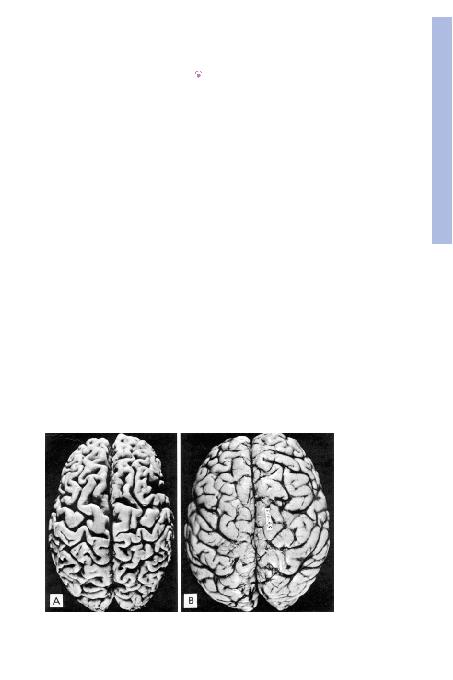

fiEKA, Aterosklerotik

hastal>¤> olan 82 yafl>ndaki

erkekte beyin atrofisi. Atrofi

yafll>l>¤a ve kan ak>m>ndaki

azalmaya ba¤l> geliflmifltir.

Meninksler ç>kar>lm>flt>r. B,

36 yafl>ndaki erke¤e ait nor-

mal beyin. Beyin maddesin-

deki azalman>n giruslar> da-

raltt>¤>, sulkuslar> geniflletti¤i

görülmektedir.